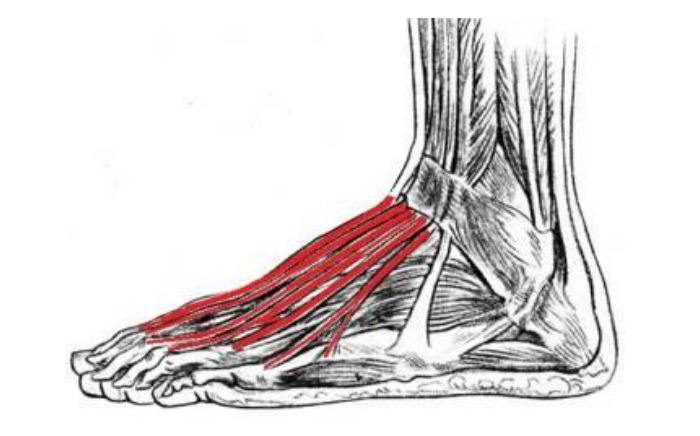

Common Foot & Ankle Disorders

Did you know the foot has 26 bones, 33 joints, 107 ligaments, 19 muscles, and numerous tendons? These parts all work together to allow the foot to move in a variety of ways while balancing your weight and propelling you forward or backward on even or uneven surfaces. It is no wonder that 75 percent of all Americans will experience foot problems at one point or another in their lifetimes.